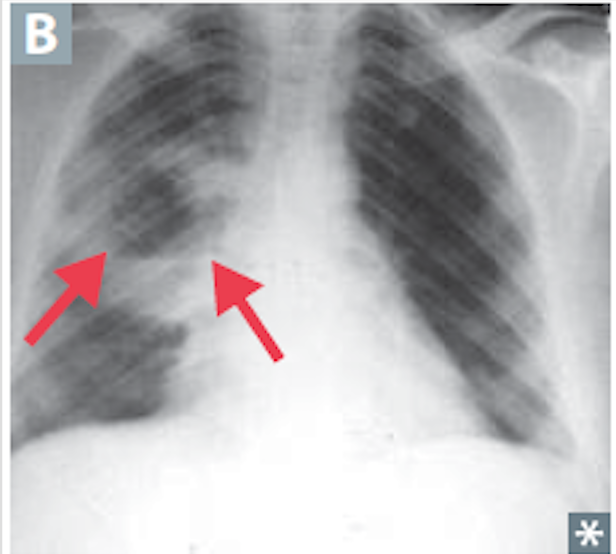

Localized collection of of PUS within parenchyma caused by aspiration of oropharengeal contents. Especially in alcoholics

Lung Abscess